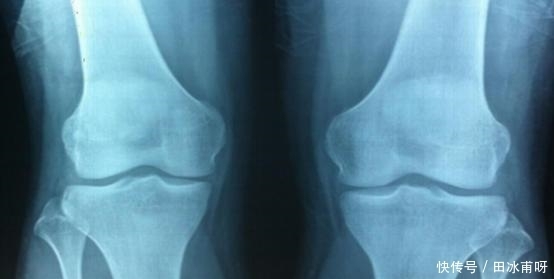

男孩变声和女孩月经初潮是标志孩子进入青春期后期。这时候骨骺已经接近闭合生长空间很小。

这个时期四肢长骨和脊椎骨均已完成骨化,身高就停止增长了。

因此当孩子在儿童期,家长一定要注意孩子生长速度,避免骨骼彻底闭合!